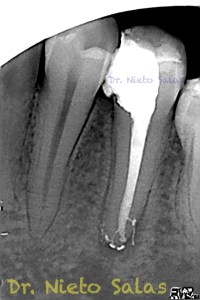

Y este sería el otro caso:

Es muy importante cambiar la proyección de las Rx para tener más información de como hemos sellado el sistema de conductos.